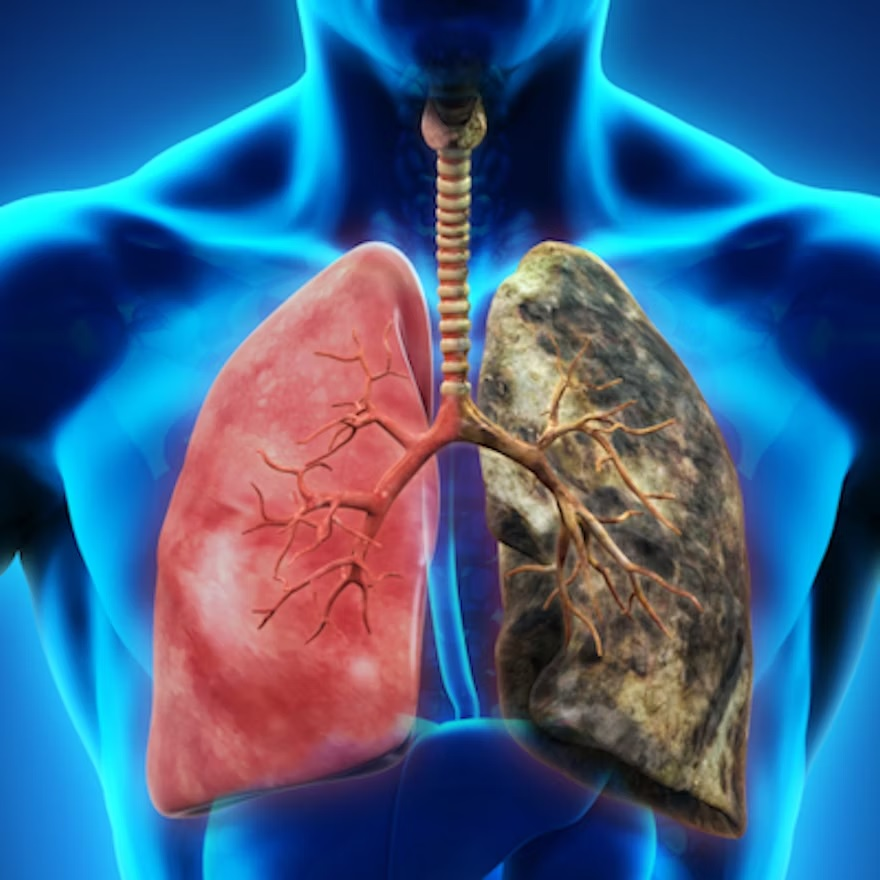

Annually, lung cancer causes more than 130,000 deaths in the U.S., more than breast, prostate, and colorectal cancer deaths combined, and 80% to 85% are attributed to smoking, he said. In 2021, the USPSTF released updated lung cancer screening guidelines that lowered the starting age from 55 to 50 and adjusted smoking history from 30 pack years to 20 pack years in an attempt to catch lung cancer earlier and address healthcare inequities among different racial and ethnic groups and between men and women. Screening uptake has increased from 8 million to 14 million adults between 2013 and 2021, he said, but more must be done to address disparities.

"Only 50% of all patients diagnosed with lung cancer would have met any prior screening criteria," he noted. "The 2021 USPSTF criteria, while improved, still lead to disparities, particularly for younger Black patients -- primarily due to pack-year requirements."